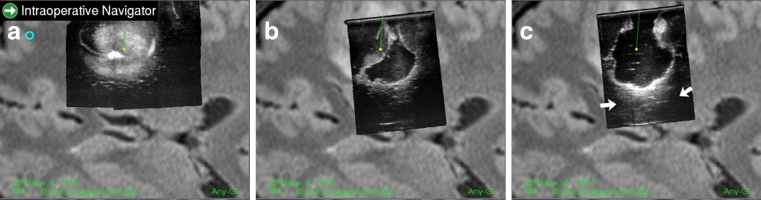

Fig. 2.

Navigation display showing the reformatted ultrasound image slices on top of the corresponding reformatted MR image slice. Ultrasound image slice from 3D ultrasound volume acquired prior to start of resection (a), towards the end of resection with some tumor tissue remaining (b), and after completed tumor resection (c). Notice the signal enhancement below the cavity (marked with arrows) seen in c, which is not observed in a or b. Hence, it is very likely that the enhancement is an artefact and not remaining tumor